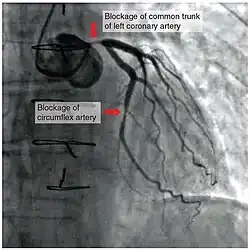

To diagnose a coronary occlusion, a doctor may view a patient's medical history, or perform a coronary angiography; a doctor will stick a catheter into the wrist or groin, lead it to the heart, and inject a liquid for X-ray imaging.[4]

To assist in a diagnosis, healthcare providers may also order a electrocardiogram (ECG or EKG), coronary calcium scan, stress test, cardiac magnetic resonance imaging (MRI), cardiac positron emission tomography (PET), invasive coronary angiography, and/or coronary CT angiography.[11]